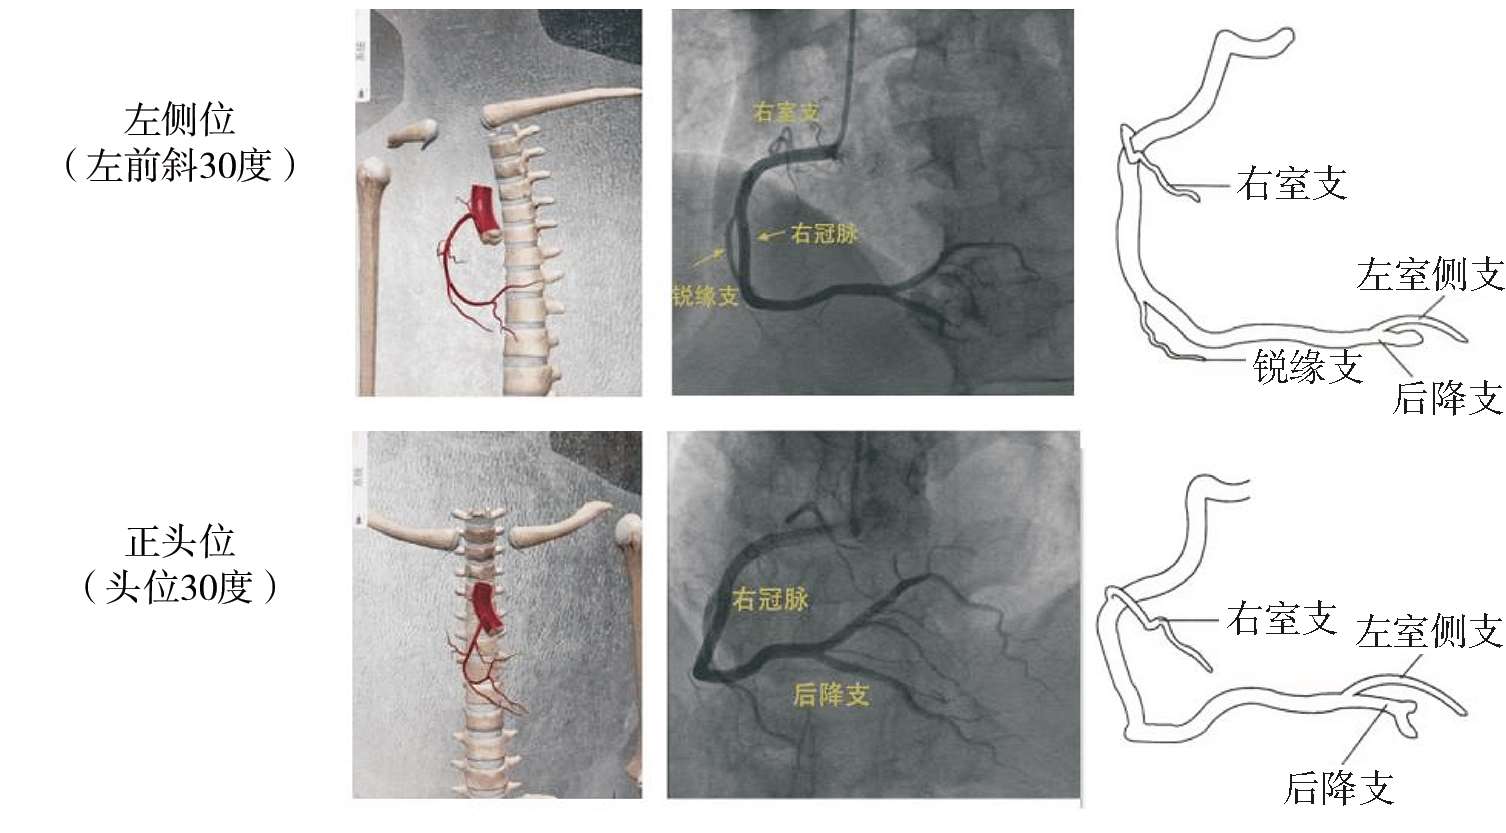

为了全面展现患者冠状动脉血管的情况,在冠状动脉造影检查过程中需要造影操作者通过踏板来控制射线,实现透视或者录像的功能。造影操作者通过检查床旁的摇杆控制C臂旋转,改变X线放射源及接收器(增强器)相对患者的位置,最后显示器上显示的造影图像会随着投照体位和角度而改变。左冠状动脉检查常用的体位有蜘蛛位、左头位、右足位和正头位(见图1-46),右冠状动脉检查常用的体位有左侧位和正头位(见图1-47)。

图1-47 右冠状动脉检查常用体位及X线下投影、走行